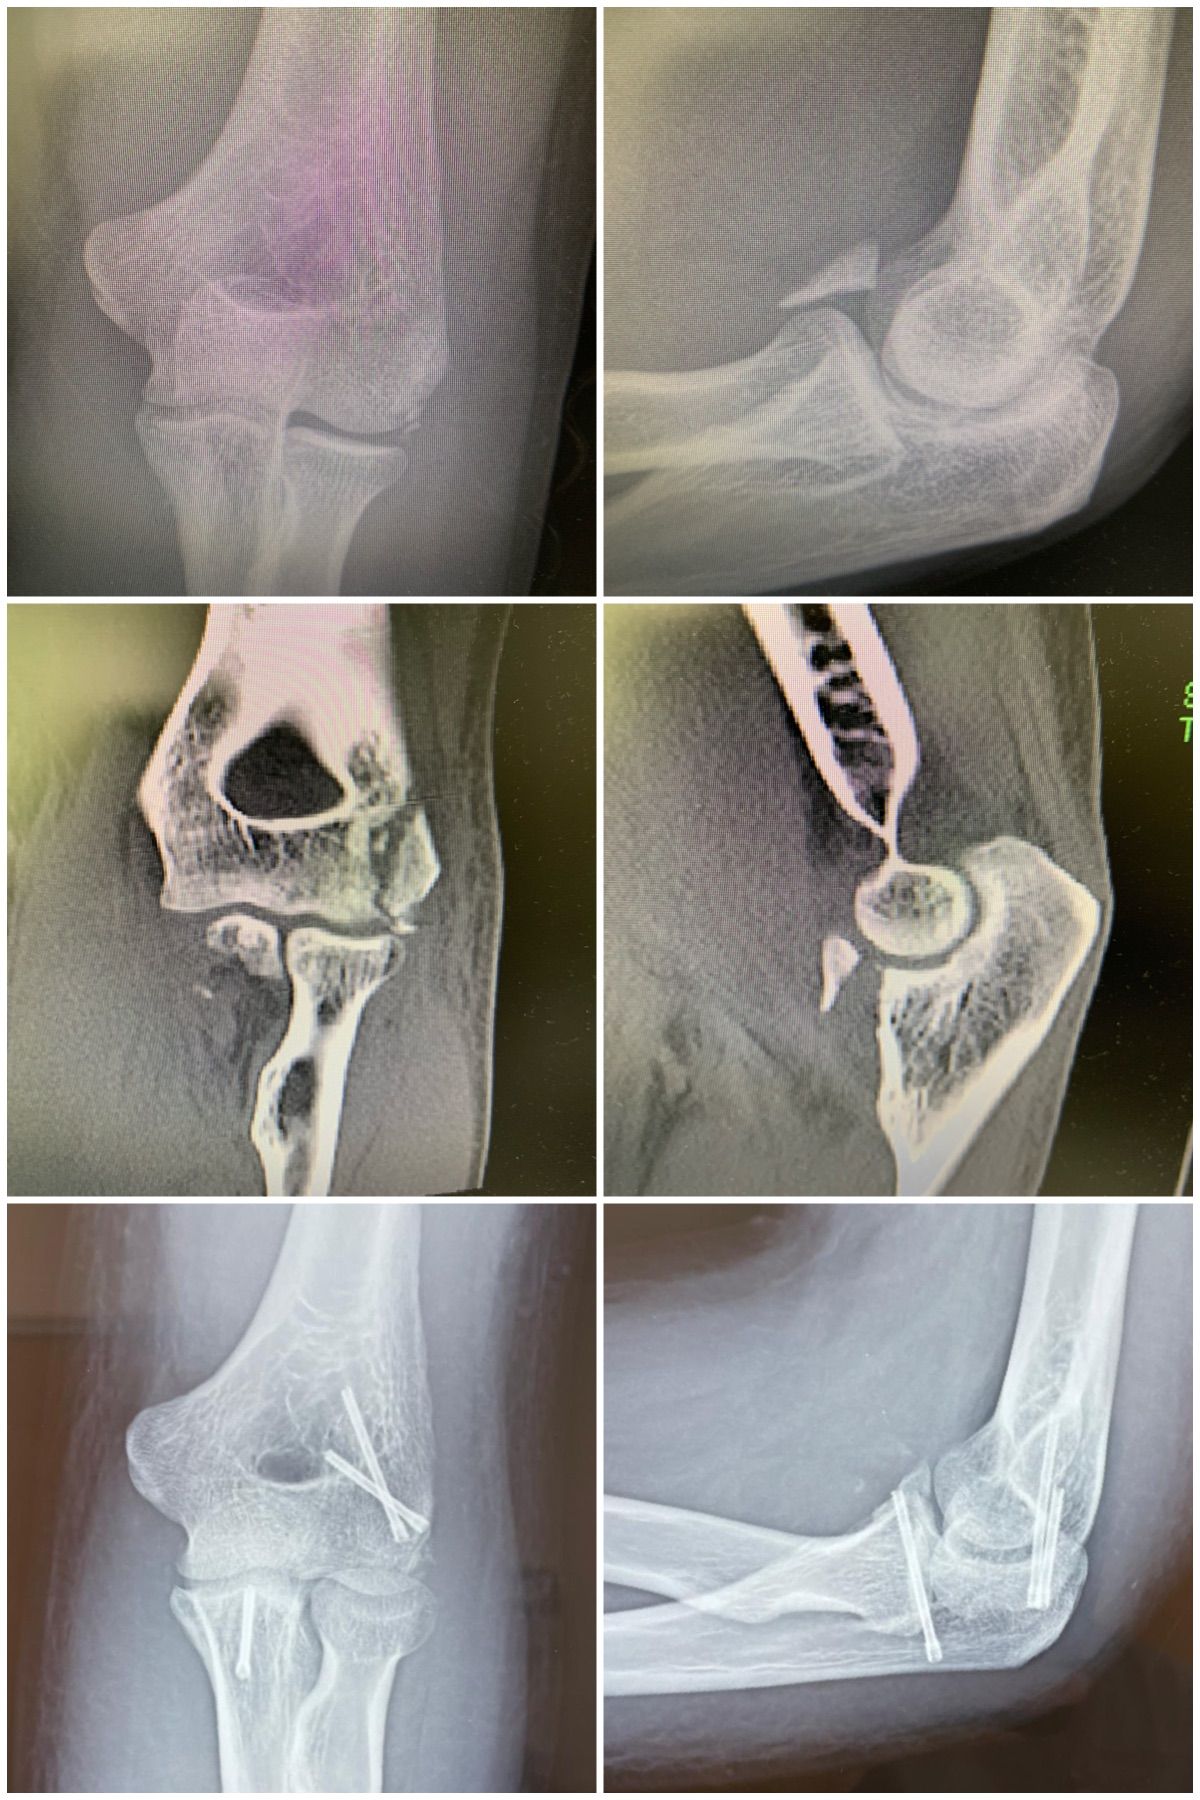

Se especializa en Síndrome del Manguito Rotador, Artroscopía de Hombro, Luxación de Hombro, Epicondilitis Lateral (Codo de Tenista), Fractura de Clavícula, Disyunción Acromioclavicular, Fracturas de Codo.

Conferencista. Tríada Terrible del Codo. II Jornadas de Traumatología. Hospital Universitario de Caracas (HUC). Caracas, Venezuela. 2015